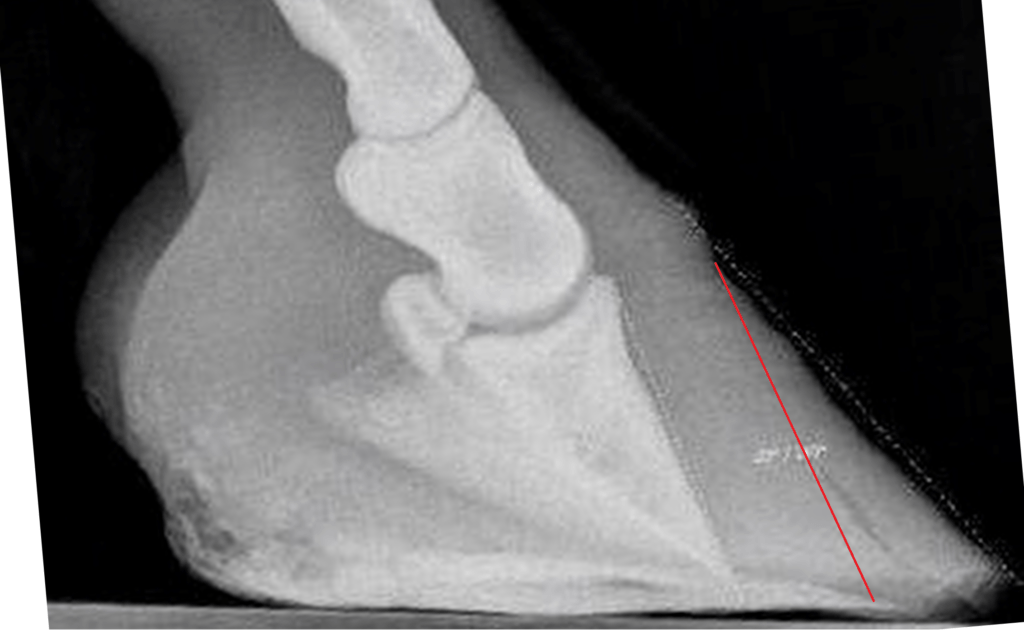

I knew the horse whose hoof appears in the following radiograph, and I know that the hoof got diagnosed with “coffin bone rotation” based on this image (which is why I have it).

If this hoof was anything but sound, it had nothing to do with anything we can see on this radiograph. The toe might be a little too long (like on most hooves), and the hoof wall is not perfectly parallel with the coffin bone (like on most hooves with long toes), but the coffin bone is almost perfectly ground parallel (which is rare). If the coffin bone has an angle of a degree or two, up or down, is of no interest since the ground is hardly ever perfectly horizontal. I drew some lines on this radiograph to indicate things that are often misunderstood, and yes, I will write a segment on the harmless misconception called NPA.